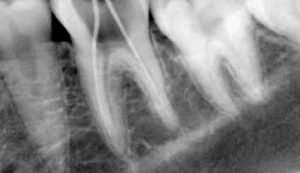

X-rays

In most cases a clinical exam by itself is not sufficient to completely diagnose all potential problems with your mouth. In fact, the majority of problems with your teeth and the jawbone are not visible to the naked eye. That is why x-rays play a key role in allowing a better, and more accurate look at what is really going on inside your mouth and below your teeth and gums. By using x-rays your dentist can check for any bone loss and determine the severity of the gum disease.

In addition to revealing any problems that were not visible during the clinical exam these initial x-rays will also provide your dentist with a benchmark with which to compare against during your future visits.